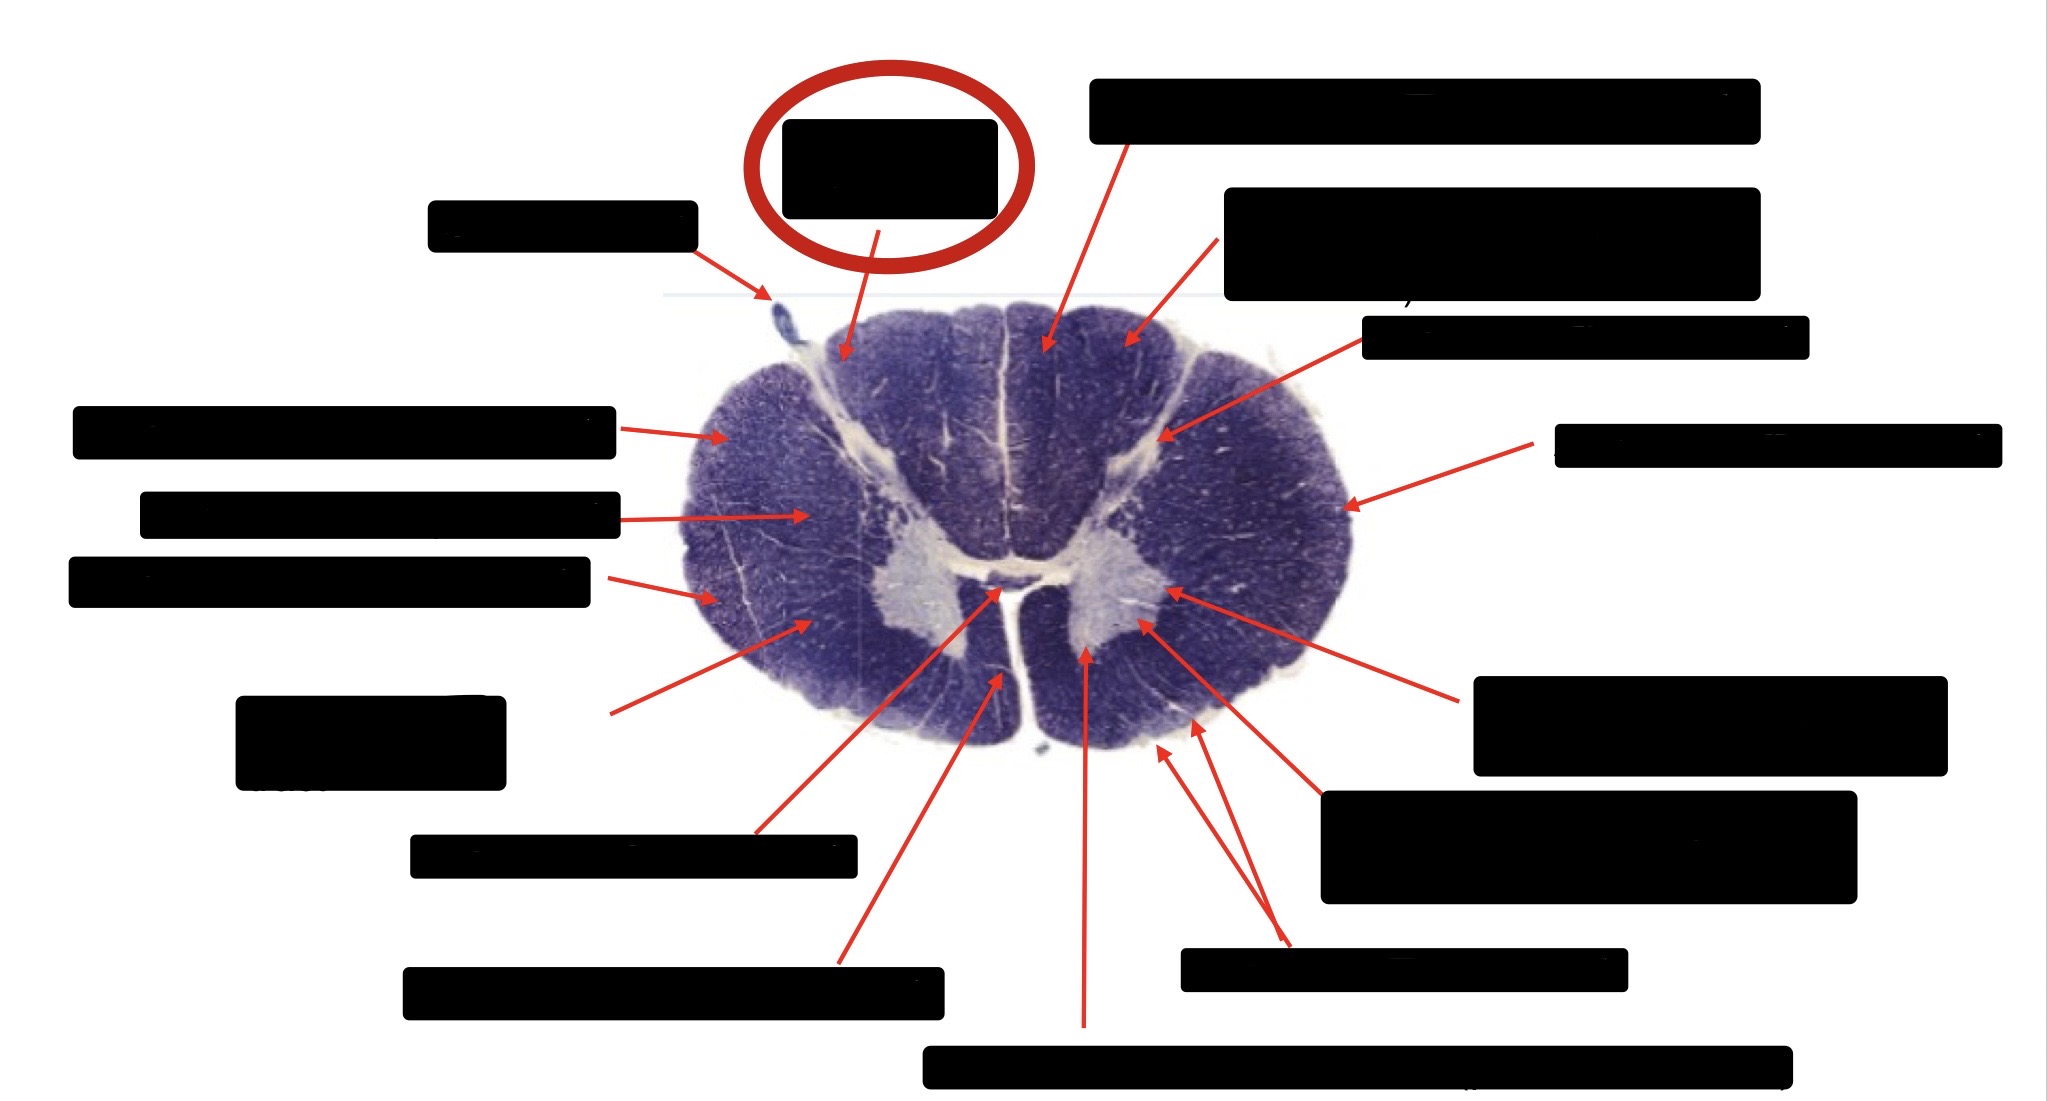

Anterior Corticospinal Tract

Large Fiber Entry Zone

Dorsal Rootlet

Posterior Spinocerebellar Tract

Lateral Corticospinal Tract

Anterior Spinocerebellar Tract

Spinothalmic Tract

Central Canal

Posterior Column (Fasciculus Gracilis)

Posterior Column (Fasciculus Cuneatus)

Substantia Gelatinosa

Accessory Nerve Fibers

Anterior Horn Motor Fibers (Accessory Muscles)

Anterior Horn Motor Fibers (Proximal Muscles)

Ventral Root Fibers

Anterior Horn Motors Neurons (Proximal Muscles)

Posterior Columns (Joint Position, Vibration, Pressure)

Fasciculus Cuneatus

Fasciculus Gracilis

Dorsal Root

Dorsal Spinocerebellar Tract

Ventral Spinocerebellar Tract

Lateral Spinocerebellar Tract (Pain & Temperature)

Ventral Root

Anterior Horn (Motor Neurons)

Distal Limb Movements

Lateral Corticospinal (Pyramidal Tract)

Rubrospinal Tract

Axial & Proximal Limb Movements

Lateral Reticulospinal Tract

Vestibulospinal Tract

Ventral Reticulospinal Tract

Tectospinal Tract

Ventral Spinthalamic Tract (Pressure Touch - Minor Role)

Ventral (Uncrossed) Corticospinal Tract (Distal Limb Movements - Minor Role)